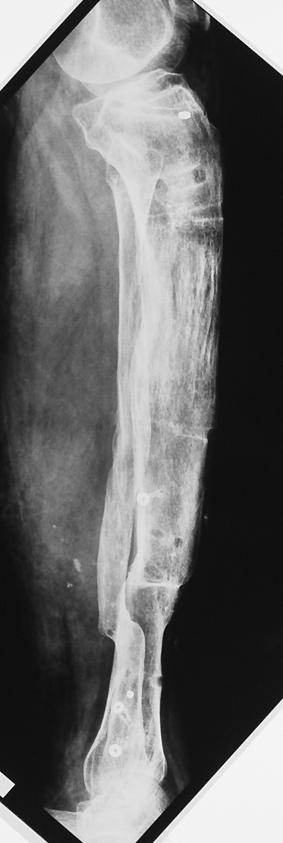

Chronic osteomyelitis leads to necrosis of bone and soft tissues. Dead bone is a nidus which hosts pathogenous microorganisms. Defence mechanisms of the host is usually not in optimum condition to deal with microorganisms. Antibiotics can’t reach the infection site because blood flow is disrupted. For these reasons, dead bone has to be completely removed by radical debridement.

Appropriate radical debridement necessitates excision of all necrotic bone and soft tissues, and frequently causes instability at the involved extremity. The remaining bone and soft tissue defect has to be fixed and reconstructed. The distraction osteogenesis method of Ilizarov is used successfully for achievement of union, correction of the deformity, elimination of limb length inequality and reconstruction of segmental bone defects.